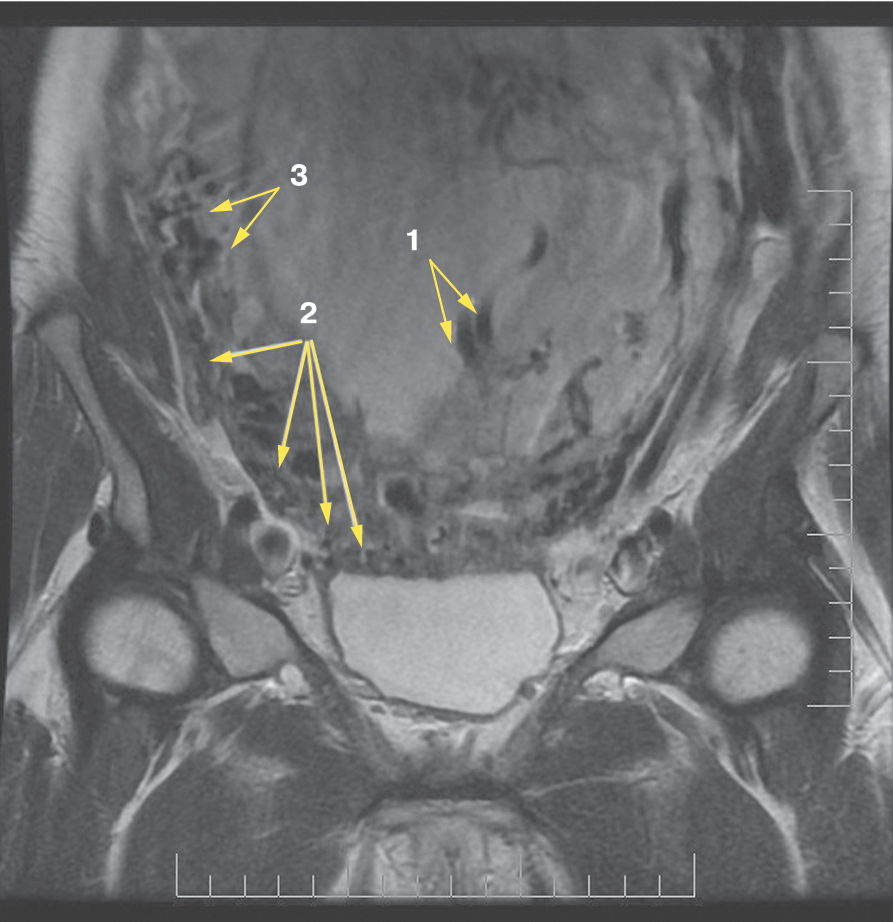

Является ли симптом «обнаженного сосуда» патогномоничным для параметральной инвазии или нет, еще предстоит выяснить; однако в ходе исследования установлена его связь с частотой гистерэктомий в группах с наличием симптома «обнаженного сосуда», что, вероятно, обусловлено мощной сосудистой сетью коллатералей и неоангиогенезом. Во всех случаях обнаружения данного признака впоследствии была выполнена вынужденная гистерэктомия (рис. 3–6, пациентка Н., 37 лет).

Рис. 6. Корональная проекция МРТ. 1 – обнаженный сосуд; 2 – интрамуральная гиперваскуляризация; 3 – гиперваскуляризация плаценты